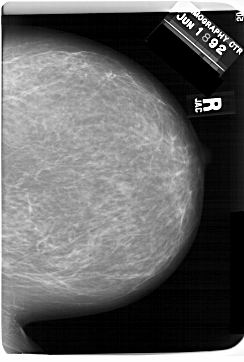

A_1560_1.RIGHT_CC

RIGHT_CC LINES 6871 PIXELS_PER_LINE 4636 BITS_PER_PIXEL 12 RESOLUTION 43.5 NON_OVERLAY